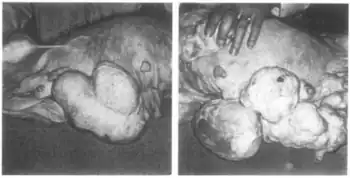

In 1966, during its clinical development, ethynerone was found to produce mammary gland tumors in dogs treated with it at very high doses for prolonged periods of time.[4][5][6] Subsequent investigation found that 17α-hydroxyprogesterone derivatives included anagestone acetate, chlormadinone acetate, medroxyprogesterone acetate, and megestrol acetate produced similar mammary gland tumors, and that their ability to do so correlated directly with their progestogenic actions.[6][7] In contrast, the non-halogenated 19-nortestosterone derivatives norgestrel, norethisterone, noretynodrel, and etynodiol diacetate, which are much less potent as progestogens, did not produce such effects at the dosages tested.[6] Clinical development of ethynerone was discontinued, and many of the 17α-hydroxyprogesterone derivatives were withdrawn for the indication of hormonal contraception.[6][7] Research later on revealed species differences between dogs and humans and established that there is no similar risk in humans.[2]